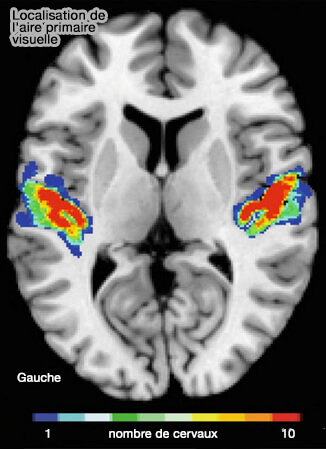

Localisation de l'aire visuelle primaire